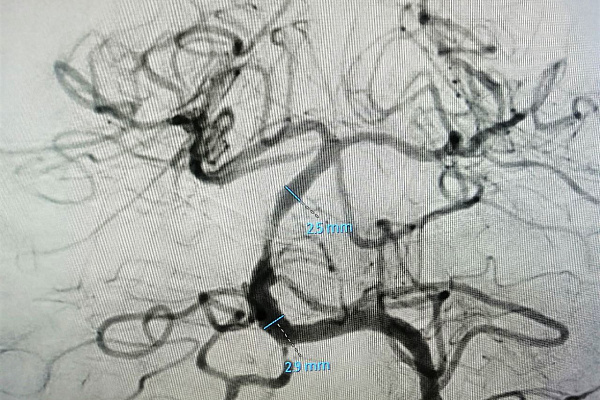

Обследование показало, что у пациента закупорен один из главных сосудов головного мозга – базилярная артерия. На фото №1 хорошо видно место, где резко обрывается кровоток. При тромбозе базилярной артерии летальность достигает 95%, а больше половины выживших обречены на глубокую инвалидность, вплоть до вегетативного состояния. Только при оказании своевременной и грамотной специализированной медицинской помощи появляются шансы на спасение. Пациента подняли в рентген-операционную, где заведующему отделением рентгенохирургических методов диагностики и лечения Максиму Бессмертных вместо планируемой одной операции пришлось в экстренном порядке выполнить сразу три.

Специалист быстро удалил тромб. Но появившийся кровоток обозначил другую проблему – субокклюзию базилярной артерии. На участке длиной 8 миллиметров она представляла собой тонкую ниточку (фото №2). При таком сужении не только не возобновилось бы полноценное питание структур головного мозга, но и вновь образовался бы тромб. Причем, закупориваться просвет начал тут же, буквально на глазах рентгенохирурга.